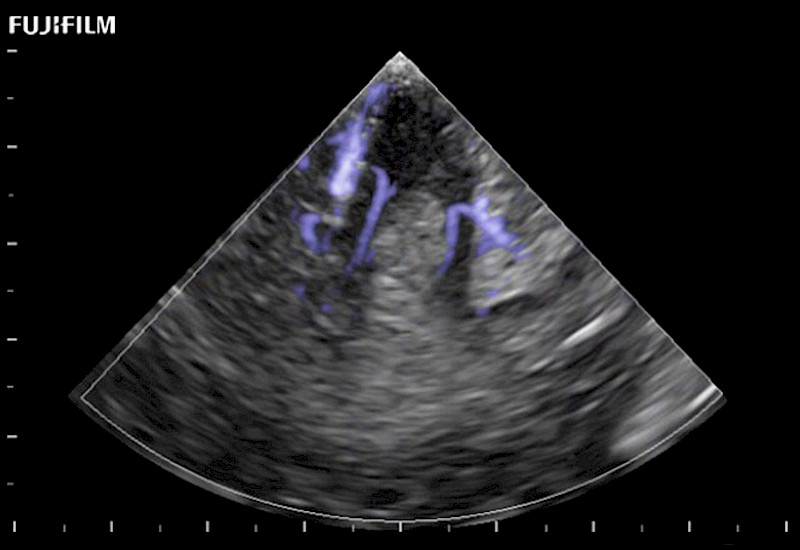

Extraordinary high-resolution digital imaging

Exceptional transducers

Multi-Parametric imaging modalities